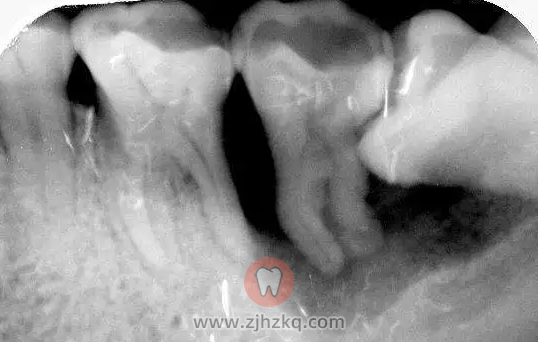

阻生智齿尽头牙图片